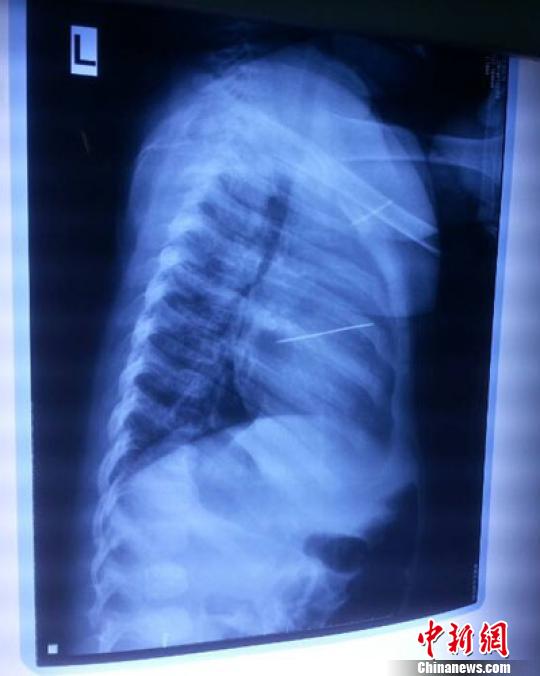

女嬰胸片提示心臟里面扎了一個縫衣針 蔡迅翔 攝

醫(yī)院胸心外科主任翟波介紹說,1月22日,小患者彤彤因為發(fā)燒抽搐來醫(yī)院就診,常規(guī)檢查時發(fā)現(xiàn)孩子心臟里面扎了一個縫衣針。

“第二天上午,我們做了個緊急彩超檢查,發(fā)現(xiàn)針是從患者右心室表面刺入,穿破室間隔,到達左心房,中間還有一部分損害到二尖瓣。于23號下午,我們就做了一個緊急手術,手術中發(fā)現(xiàn),這枚針已經(jīng)刺入心臟,沒入了右心室的下面,表面已經(jīng)看不到針了,僅能看到一個小針眼,還在往外滲血,一點一點的滲,心包腔里面大概有100多毫升的出血,心包上一個洞,針在右心室表面刺入以后,穿過室間隔,在二尖瓣的上方,進入了左心房,在針的四周,有很多纖維沉積物,包繞著這枚針?!钡圆ㄕf,他們把針取出來以后,測量了一下,長度大概是五厘米,同時發(fā)現(xiàn)這個針給患者左心房的后壁造成了一定的損傷,左心房的后壁已經(jīng)損傷了三分之二,還剩下有左心房的外膜,很薄的一層,如果這一層再破的話,這個孩子將會引起大出血,很快就會死亡。